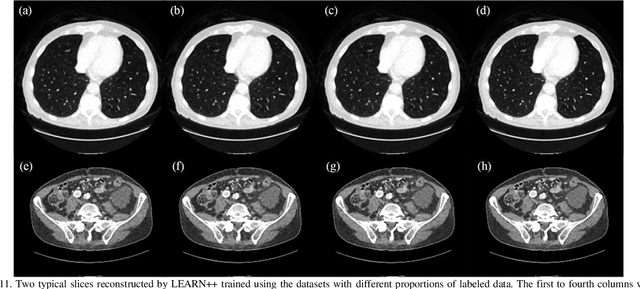

Abstract:Compressed sensing (CS) computed tomography has been proven to be important for several clinical applications, such as sparse-view computed tomography (CT), digital tomosynthesis and interior tomography. Traditional compressed sensing focuses on the design of handcrafted prior regularizers, which are usually image-dependent and time-consuming. Inspired by recently proposed deep learning-based CT reconstruction models, we extend the state-of-the-art LEARN model to a dual-domain version, dubbed LEARN++. Different from existing iteration unrolling methods, which only involve projection data in the data consistency layer, the proposed LEARN++ model integrates two parallel and interactive subnetworks to perform image restoration and sinogram inpainting operations on both the image and projection domains simultaneously, which can fully explore the latent relations between projection data and reconstructed images. The experimental results demonstrate that the proposed LEARN++ model achieves competitive qualitative and quantitative results compared to several state-of-the-art methods in terms of both artifact reduction and detail preservation.